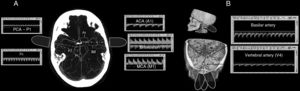

Through the temporal window, introducing a slight angulation to the transducer, the first vessel to be identified is the middle cerebral artery (MCA), between 30 and 60mm, with a flow signal towards the probe. Following the path of the MCA to a depth of 60–65mm, a bidirectional flow pattern corresponding to the bifurcation of the internal carotid artery (ICA) was sought. At this point, directing the ultrasound beam slightly in the cephalic direction and forward, the proximal segment (A1) of the anterior cerebral artery (ACA), in which the direction of blood flow is away from the probe, was examined. Next, decreasing the depth until a bidirectional pattern, corresponding to the carotid bifurcation, was encountered and directing the ultrasound beam slightly rearward and in a caudal direction, at a depth between 65 and 70mm, the precommunicating segment (P1) of the posterior cerebral artery (PCA), in which the direction of flow is towards the probe, was located. At this point, inclining the transducer slightly rearward and deepening to 70mm, the postcommunicating segment (P2), in which the direction of flow is away from the probe, was located (Fig. 1A).

(A) Ultrasound of each arterial segment of the circle of Willis, represented on cranial computed tomography angiography in an axial plane, showing the inclination of the ultrasound probe through the temporal window. (B) Ultrasounds of the vessels of the posterior circulation through the transforaminal window.

The extracranial internal carotid artery (eICA) was identified by ultrasound through the submandibular window, placing the 2mHz probe within the sternocleidomastoid muscle at a depth of 50mm. The study was completed by determining the flow velocities (FV) in the V4 segments of the vertebral arteries and the basilar artery through the transforaminal window (Fig. 1B). The peak systolic velocity (PSV), end diastolic velocity (EDV), mean flow velocity (MFV) and Gosling's pulsatility index (PI) were recorded for all arterial segments. The TCD examination was performed by the first author, who has prior training in neurosonology techniques and more than five years of experience.